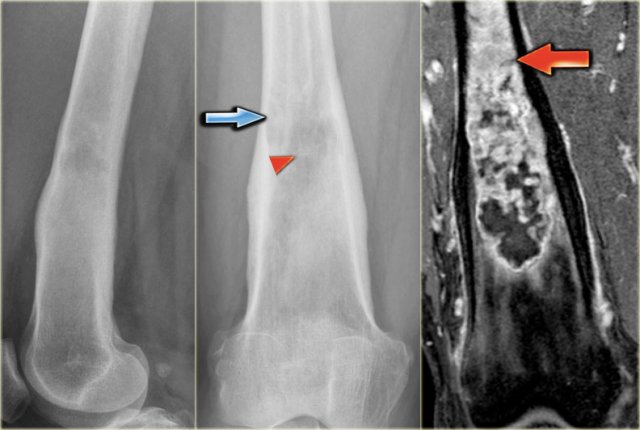

ABC (6) - atypical case

On the left two different patients with an intracortical or subperosteal osteolytic well-defined lesion in the tibia.

The lesion on the far left was thought to be an adamantinoma because of the localisation in the anterior tibial cortex.

At biopsy it proved to be an ABC.

The image on the right is an adamantinoma.